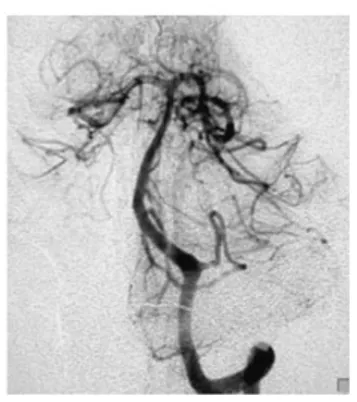

急诊头颅CT检查结果显示:第四脑室内出血。进一步行脑血管造影后发现,此次出血的"元凶"是位于左侧小脑后下动脉(PICA)的一枚动脉瘤。

结合患者的出血部位与动脉瘤特点,医生团队决定采用经髁入路实施动脉瘤夹闭手术。这一入路是颅底外科的经典术式,能够充分暴露小脑后下动脉及脑干侧方结构,同时手术创伤相对较小。

术后复查脑血管造影证实,动脉瘤已被成功夹闭,出血风险解除。术后病理报告亦表明,这枚偶然发现的肿瘤为Antoni A/B混合型神经鞘瘤。